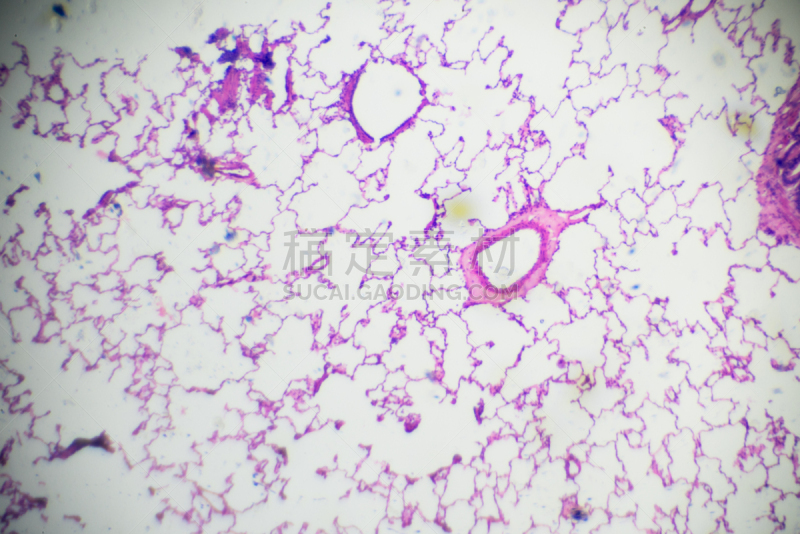

详情

详情

详情